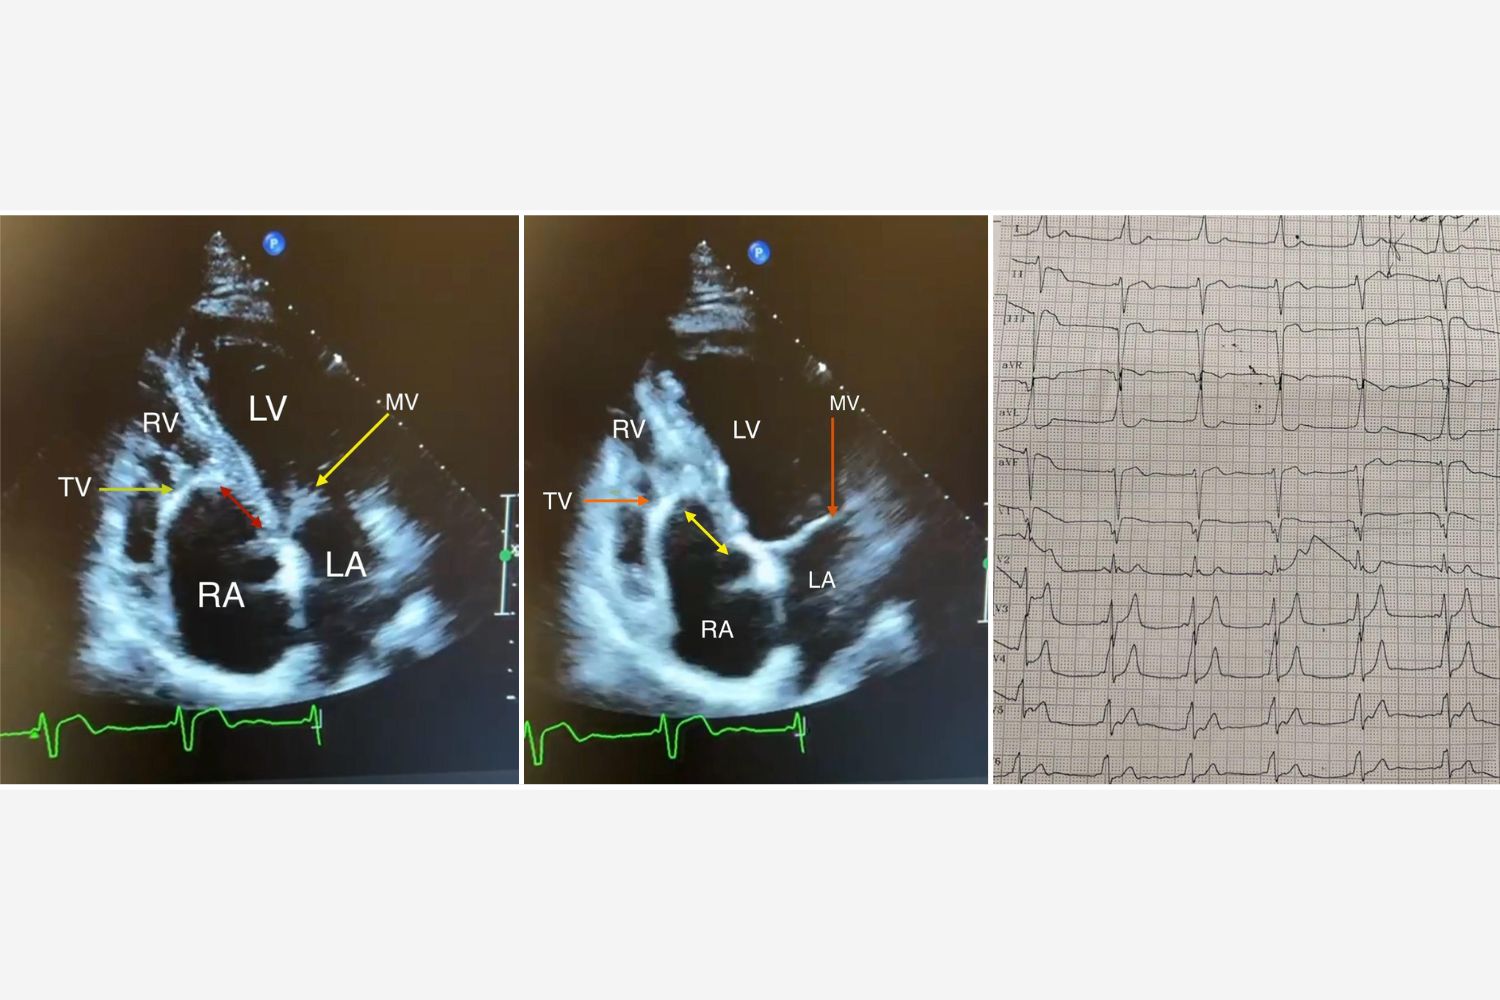

Image of the Week - 12 November 2025

Doctor Ahmed Khalil

Doctor Mina Youssef